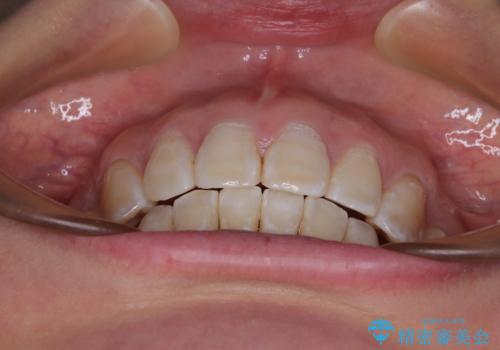

- 上顎歯列の出っ歯を気にして来院された患者様です。

骨格的に上顎歯列が前方位にあり、口元の突出感が顕著な状態で、上下左右の第一小臼歯4本を抜歯して、ワイヤー装置での抜歯矯正を行うこととしました。

ご本人がびっくりするくらい劇的に口元の突出感が改善され、大変満足のいく仕上がりとなりました。